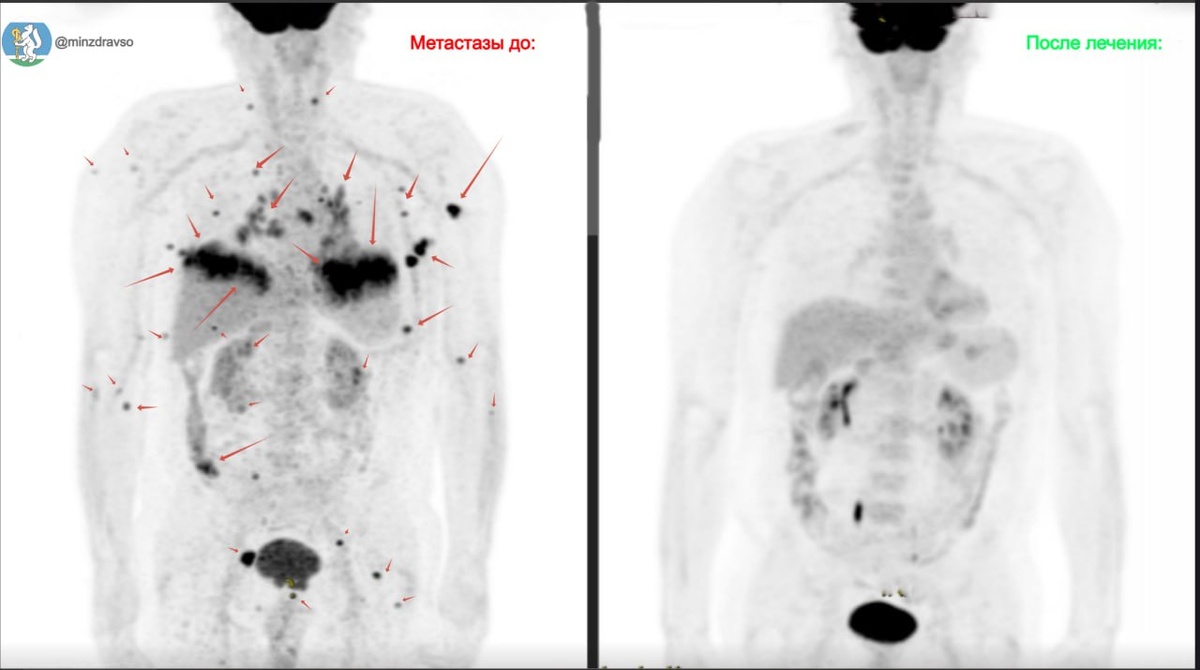

🙏Врачи Свердловского областного онкологического диспансера благодаря комплексному лечению смогли достичь стойкой ремиссии у пациента с четвёртой стадией меланомы.

Впервые меланому у свердловчанина диагностировали в 2015 году. Успешное лечение позволило достичь ремиссии длинною в восемь лет. В 2023 году случился рецидив заболевания, и мужчине удалили опухоль и около 30 метастазов в лимфоузлах.

🧬Пациенту провели курс лекарственного лечения для снижения риска развития рецидива, однако спустя полгода злокачественное новообразование вернулось. Множественные очаги образовались в костях и в лёгких, удалить их хирургическим путём не представлялось возможным, а на медикаментозную терапию организм «не отвечал». 😱

Тогда онкологи проверили один из очагов опухоли на генетическую мутацию BRAF.

«В некоторых случаях клетки опухоли могут изменять свою структуру — мутировать. Данного пациента в начале лечения уже проверяли на генетическую мутацию BRAF, но исследование было отрицательным. При повторной морфологической диагностике оказалось, что опухоль изменила структуру, и появился шанс применить для её лечения таргетную терапию», — объяснил лечащий врач пациента, онколог СООД Роман Аристов.